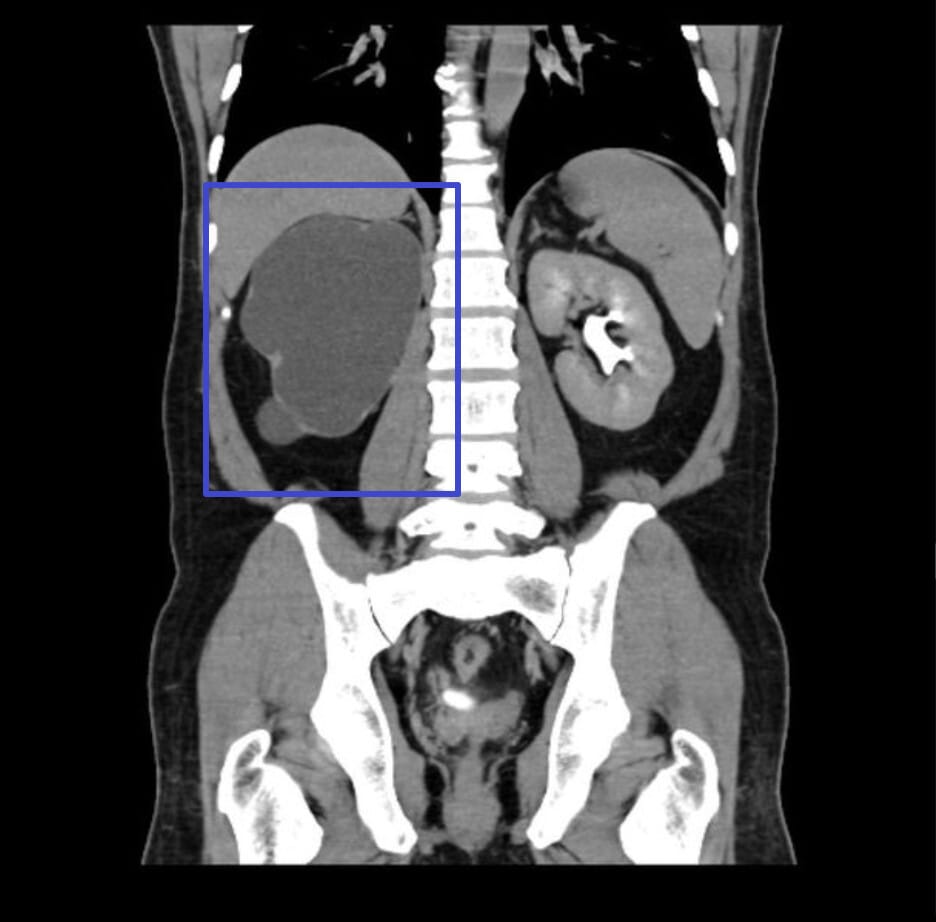

| 🔵 비조영 CT (CT KUB) |

| 요석 유무를 확인하는 데 가장 정확하며, 급성 폐쇄 원인 평가에 유용합니다. |

수신증의 영상은 확장된 신우/신배 및 폐쇄 위치 확인.

| 🔍 특징적 영상소견 요약 |

| ✅ 신우 및 신배의 확장 |

| 초음파 또는 CT에서 신장 내부가 검고 넓게 확장되어 보입니다. |

| ✅ 신실질 위축 |

| 만성 수신증에서는 신피질이 얇아지고, 전체 신장 크기가 감소할 수 있습니다. |